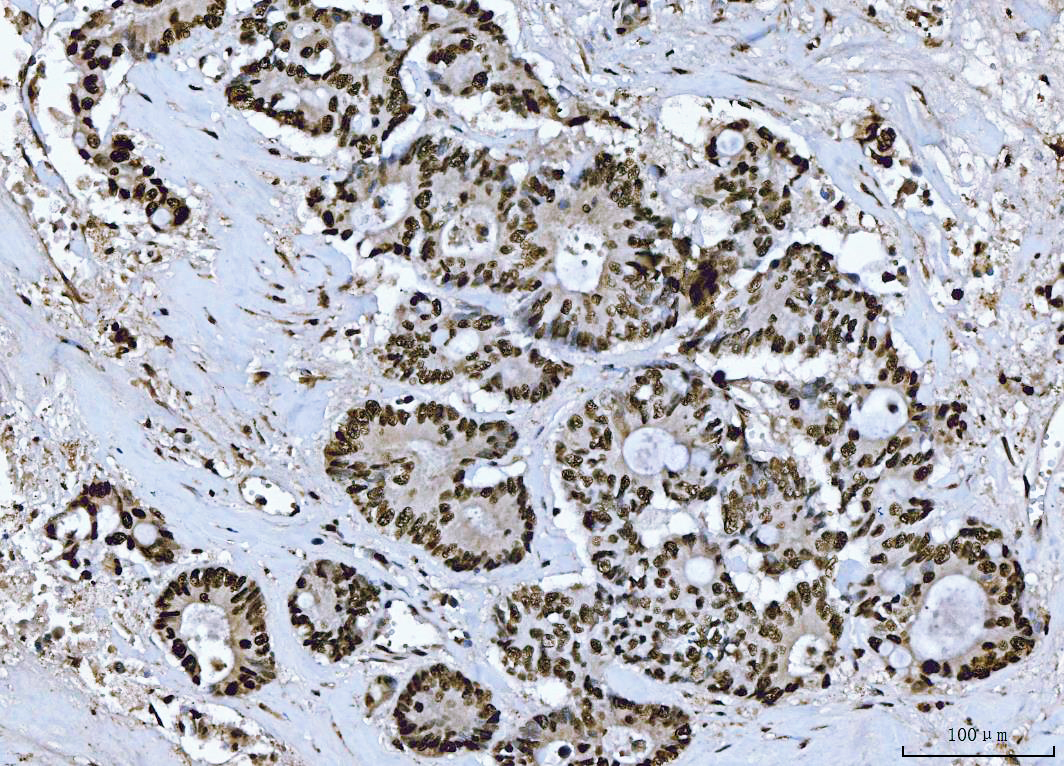

IHC analysis of BRCA1 using anti-BRCA1 antibody (PB9015).

BRCA1 was detected in a paraffin-embedded section of human colorectal adenocarcinoma tissue. The tissue section was incubated with rabbit anti-BRCA1 Antibody (PB9015) at a dilution of 1:200 and developed using HRP Conjugated Rabbit IgG Super Vision Assay Kit (Catalog # SV0002) with DAB (Catalog # AR1027) as the chromogen.